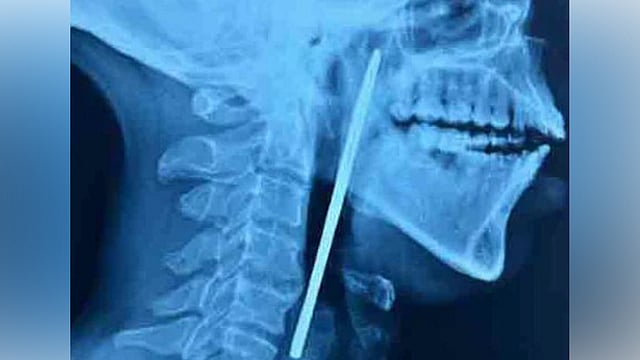

എക്സറേയിൽ അന്നനാളത്തിൽ കത്രിക കുടുങ്ങി കിടക്കുന്നതായി പരിശോധിച്ചപ്പോൾ കണ്ടെത്തി. തുടർന്നു യുവാവിനെ ഇഎൻടി വിഭാ​ഗത്തിൽ പ്രവേശിപ്പിച്ചു. പിന്നാലെ തിങ്കളാഴ്ച രാത്രി നടത്തിയ ശസ്ത്രക്രിയയിലൂടെ 15 സെന്റി മീറ്റർ നീളമുള്ള കത്രിക പുറത്തെടുക്കുകയായിരുന്നു.

ഇഎൻടി വിഭാ​ഗത്തിലെ ഡോ. ശ്രീജിത്തിന്റെ നേതൃത്വത്തിലാണ് ശസ്ത്രക്രിയ നടന്നത്. രോ​ഗിയുടെ ആരോ​ഗ്യനില തൃപ്തികരമാണെന്നു മെഡിക്കൽ കോളജ് അധികൃതർ വ്യക്തമാക്കി.